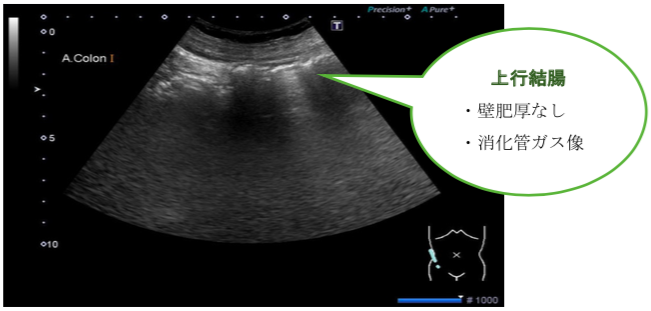

新超音波検査 消化管 新超音波検査 消化管 | 関根 智紀 |本 | 通販 | Amazonの詳細情報

新超音波検査 消化管 | 関根 智紀 |本 | 通販 | Amazon。新超音波検査消化管。消化管エコーの最新動向 - 新。超音波診断 Vol.03 - 東芝。

超音波でみる病気の腸(小腸・大腸)」腹部超音波検査Vol.9-2

新超音波検査消化管

関根智紀

2006/05/25

4902380218

9784902380217

超音波でみる病気の腸(小腸・大腸)」腹部超音波検査Vol.9-2